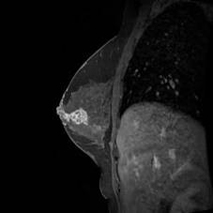

近年、食生活などの変化の影響で12人に1人が乳がんにかかると言われています。乳房撮影装置は、乳房専用の装置で、乳房をはさんで薄くのばし、緻密な構造(乳腺・石灰化・腫瘤など)を描出するため、非常に有用です。早い段階で約90%治癒される乳がんにとって、マンモグラフィ撮影は、必須項目です。また、早期発見は、女性にとって精神的苦痛とも言える「乳房全摘術」を行わず「乳房温存療法」が可能となります。マンモグラフィは、触診などで分かりにくい早期の乳がんや、微小石灰化病変・乳管拡張病変などの発見に最適な検査です。

当院では、マンモグラフィ精度管理中央委員会認定の乳房撮影装置Senographe Pristinaを2017年2月に導入しました。高画質で低線量をハイレベルで両立し、かつ乳房圧迫時の痛みを少しでも軽減できる特徴を持っています。また、この装置は新しい技術であるトモシンセシスが可能です。トモシンセシスとは、従来のマンモグラフィ撮影に加え、X線管球を移動させながら連続的に撮影し、収集した画像データを3次元的に再構成後、見たい構造に焦点を合わせた画像の提供が可能な技術です。従来を2Dマンモグラフィとすれば、トモシンセシスは3Dマンモグラフィということになります。従来の撮影(2D撮影)では、乳腺内に隠れて見えなかった病変も、高画質なトモシンセシス(3D撮影)により見つけ出しやすくなります。

当院では、精度管理中央委員会認定の女性の放射線技師が撮影し、認定医師が診断し、乳がんの早期発見に努めています。